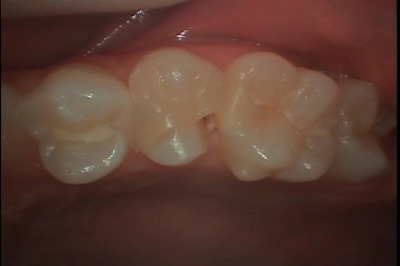

上顎第二小臼歯の深い虫歯に対しCERECでセラミック修復を行った例

今回は深い虫歯に対しCERECでセラミック修復を行った例をご覧下さい。

患者さんは都筑区にお住まいの10代の女性の方で、虫歯治療を希望して来院されました。

口腔内所見としては、左上第二小臼歯に以前に行われた充填物があり、その横に穴があいています。

口腔内写真1でも大きな問題は無いように見えます。

しかし拡大鏡装着下で見ていくと口腔内写真2のように何やら怪しい所が見えてきます。